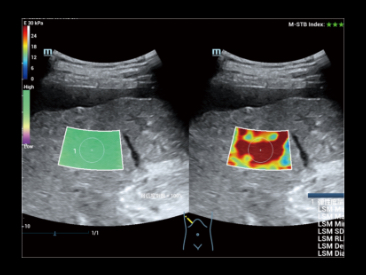

ZST+

Технология зонного сканирования.